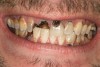

Joe soon learned how to manufacture the drug. His need for meth soon consumed his every thought. He basically lived to do more meth. He admitted that he had made some poor choices. Unfortunately once the addiction kicked in, he no longer had a choice, he had to use. This was his end result (Figure 4 through Figure 6). From these photographs, one might think that he had used the drugs his entire life; however, this progression happened over the course of only about 1 year of smoking the drug. Because of the caustic chemicals (muriatic acid, hydrochloric acid, lithium, etc) his teeth started to blacken, then break.

Figure 4  PRESENTATION CONDITION By the time Joe presented for treatment after serving time in prison and going to rehab, his teeth were completely destroyed by rampant decay. Although some teeth could have been saved, the patient chose to have all of the remaining teeth extracted in order to receive a set of full dentures.

Figure 4

Figure 5  PRESENTATION CONDITION By the time Joe presented for treatment after serving time in prison and going to rehab, his teeth were completely destroyed by rampant decay. Although some teeth could have been saved, the patient chose to have all of the remaining teeth extracted in order to receive a set of full dentures.

Figure 5